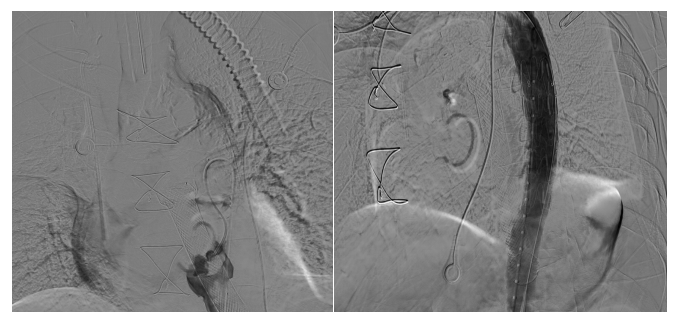

在与患者家属充分沟通并征得同意后,方主亭副院长带领陈示光主诊团队迅速、精准实施了手术。术中清晰显示造影剂从胸主动脉破口流入食管。经过一系列精细的介入操作,支架成功贴合胸主动脉,精准隔绝破口。术后造影确认破口已被有效封闭,张先生呕血、黑便等消化道出血症状消失,血红蛋白水平逐渐回升,急性上消化道大出血得到了有效控制。